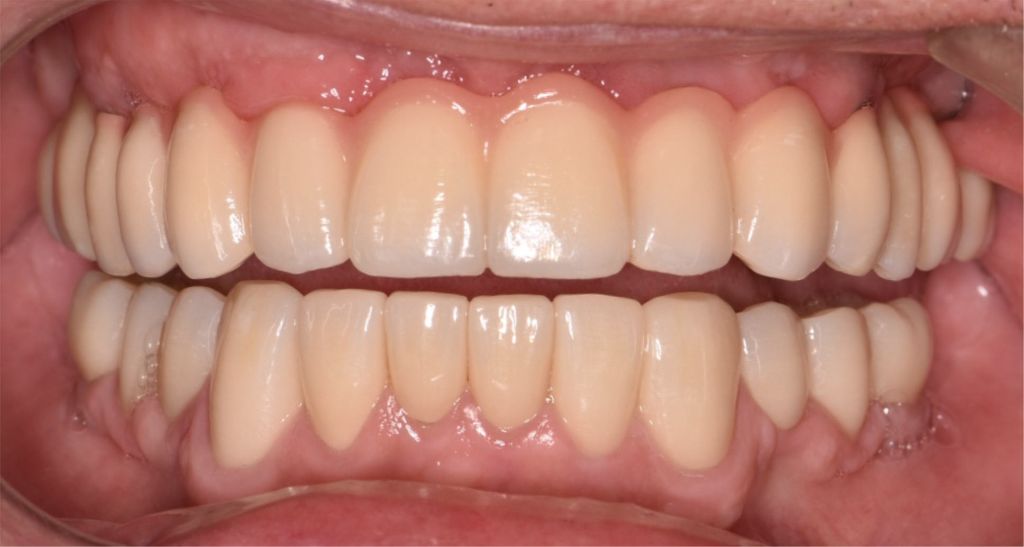

After